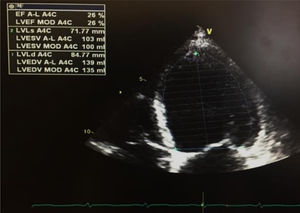

Na primeira avaliação laboratorial venosa realizada foi constatada elevação do nível de troponina I (2,01 ng/mL; normal < 0,02 ng/ml), com um pico máximo de 3,23ng/ml, 12 horas após admissão. O proBNP era de 17316 pg/ml (N < 125). O doente negava dor torácica, atual ou prévia, ou quaisquer sintomas de insuficiência cardíaca. O exame objetivo não demonstrava sinais de patologia cardiovascular, nomeadamente sem sopros ou extrassons à auscultação cardíaca, sem fervores à auscultação pulmonar, sem organomegálias à avaliação abdominal e sem edemas dos membros inferiores. O eletrocardiograma encontrava‐se em taquicardia sinusal (FC 109bpm), com retificação do segmento ST em V5, V6, I e aVL. Um ecocardiograma transtorácico (ETT) foi requisitado, e realizado no dia da admissão, em ecógrafo portátil Vivid I GE, demonstrando um ventrículo esquerdo não dilatado, não hipertrofiado, com um compromisso grave da função sistólica ventricular esquerda, estimada em 26%, devido a hipocinesia difusa; sem doença valvular aórtica ou mitral significativa; ventrículo direito com função sistólica longitudinal conservada, veia cava inferior (VCI) de 17mm, com cinética respiratória mantida e pressão da artéria pulmonar estimada em 28mmHg (Figura 1).